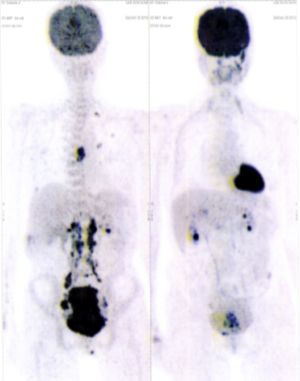

CASE NO: 1 - A FEW MONTHS LATER

A few months after successful treatment for hepatocellular carcinoma, and partially successful for stomach cancer, the PET/CT scan showed the stomach cancer becoming very active, with several metastases to the parts of the liver not previously involved by hepatocellular carcinoma. After a few treatment, all the active stomach cancer lesions in the stomach and in the liver went into remission.